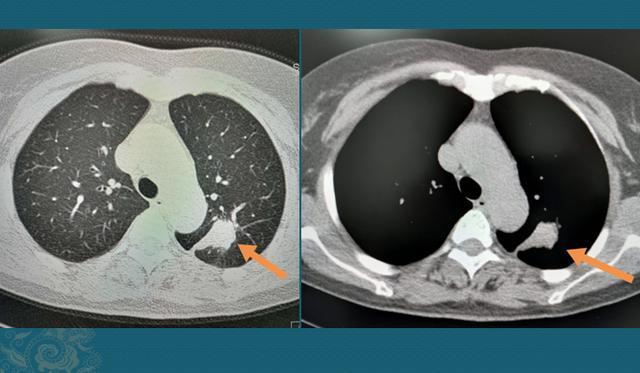

我们先不争论,看个病例,原本有手术根治机会的肺鳞癌:

图片

这是一位68岁男病人,2016年因为冠心病住院查出肺小结节,0.4cm的实性结节,建议定期复查。1年后发现肺结节增大,危险等级提升为高危肺结节,建议积极处置。

病人还是选择继续观察,2018年复查结节有轻微缩小、变形,并可见一个小囊泡,提示小气道有不完全性阻塞(肿瘤细胞沿小气道壁生长,造成管腔狭窄),建议积极处置。

病人还是选择观察。到了2019年,癌细胞繁殖出一定体量,开始露出尖锐的獠牙:

从2018-2019的一年时间里,迅速长成分叶状肿块,并且与胸膜建立联系,沿着胸膜出现了小结节灶,穿刺病理是低分化肺鳞癌,已经错过了最佳手术机会……

癌症的生长速度不是匀速的,通常会有一个加速期,我们强调早期治疗就是要扼杀住这个加速期,规避癌细胞的爆发式播散。